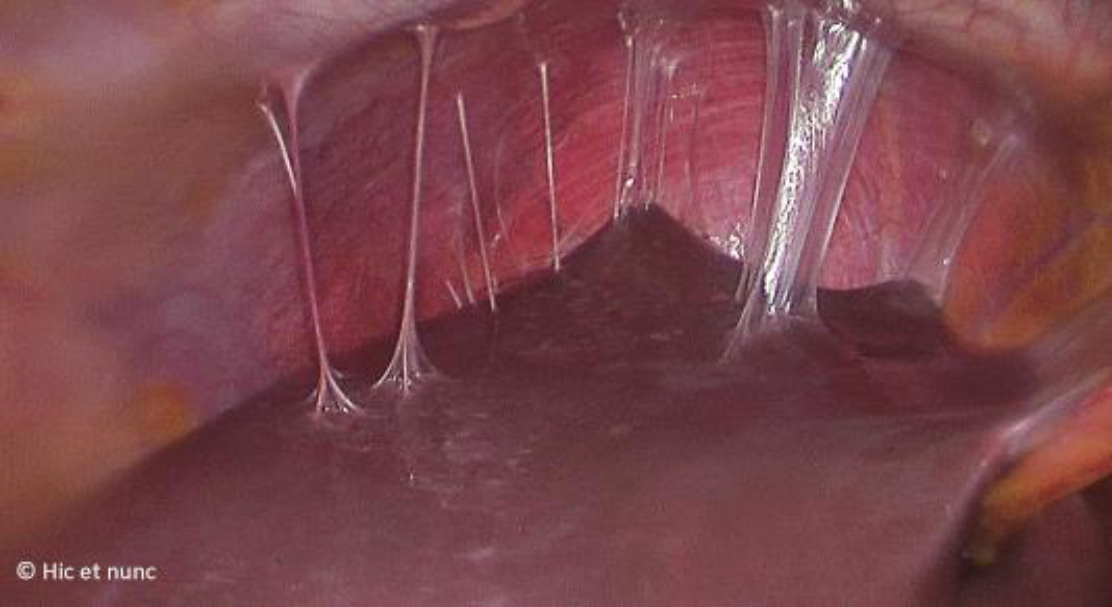

Vous décidez de réaliser en urgence une cœlioscopie exploratrice qui objective un saignement modéré au niveau du kyste de l’ovaire que vous parvenez difficilement à arrêter. En explorant la cavité abdominale vous objectivez ceci (fig. 7) :

Figure 7

Question 7 - Quelles sont les réponses vraies (une ou plusieurs réponses exactes) ?

Les adhérences « en cordes de violon » entre le foie et le péritoine sont typiques d’une périhépatite secondaire à une infection active ou à un antécédent d’infection à Chlamydia. Il s’agit d’un syndrome de Fitz-Hugh-Curtis.

On réalise des tests par PCR (polymare chain reaction) du gonocoque et de Chlamydia sur le prélèvement vaginal et non des cultures.

On ne réalise pas de sérologies gonocoque ou Chlamydia. Ces infections ne sont pas immunisantes.

Les infections génitales hautes peuvent entraîner des adhérences et la destruction des cils tubaires qui augmentent le risque d’infertilité et de grossesse extra-utérine.